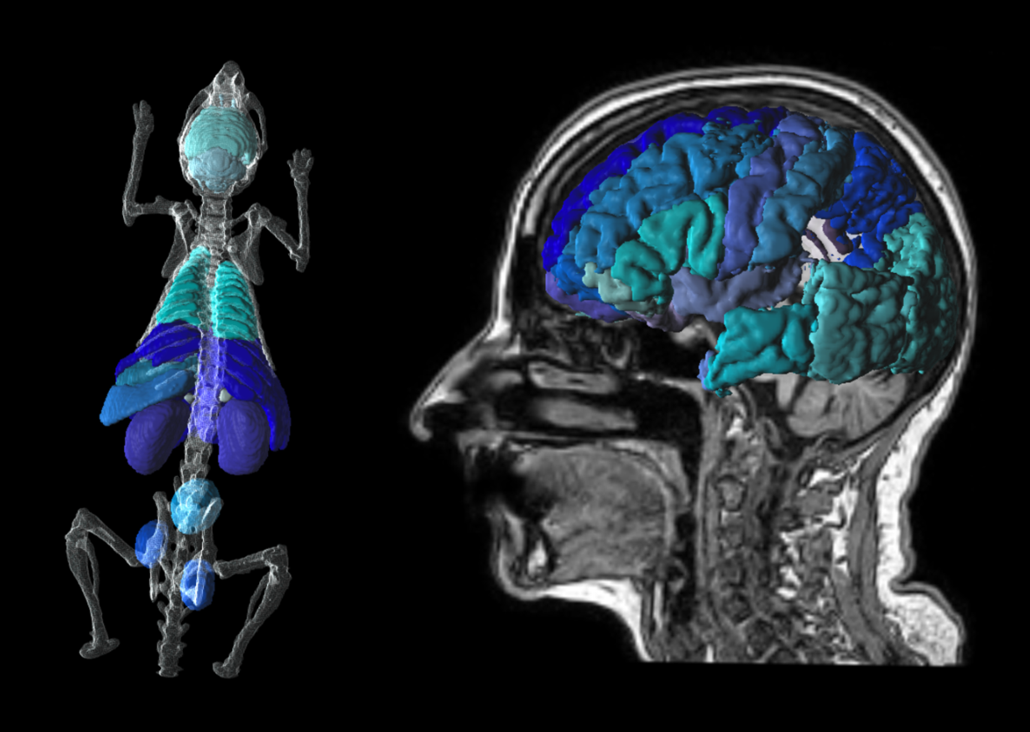

Leggi di piùPNROD Rodent Brain Analysis

PNEURO Human Brain Analysis

This tool for the analysis of PET, MR and PET/MR brain images enables workflow-based brain atlases for humans, primates and pigs.

AI-based segmentation of deep nuclei with PAI.

PET partial-volume correction, and direct connection to parametric mapping.

Supports batch processing.

Recommended in combination with PKIN, PXMOD, PAI, PFUS, P3D